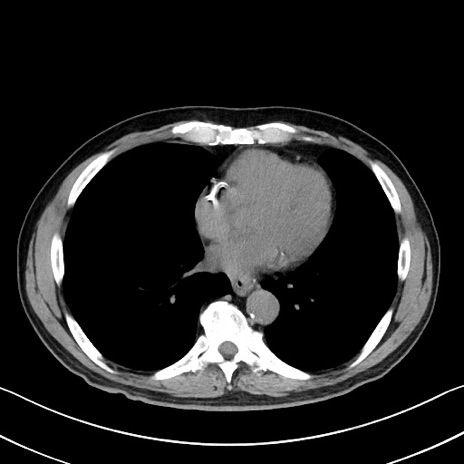

症例35(横断像)

【症例】70歳代 男性

【主訴】腹部膨満、嘔吐

【現病歴】昨日より腹部膨満感出現。本日増悪し、仙痛出現。嘔吐あり、受診。

【既往歴】糖尿病、胆摘後

【身体所見】BP 149/80mmHg、HR 74/min、BT 35.9℃、腹部:膨満、軟、圧痛なし。腸雑音減弱あり。上腹部正中切開瘢痕あり。

【データ】WBC 13500、CRP 1.72